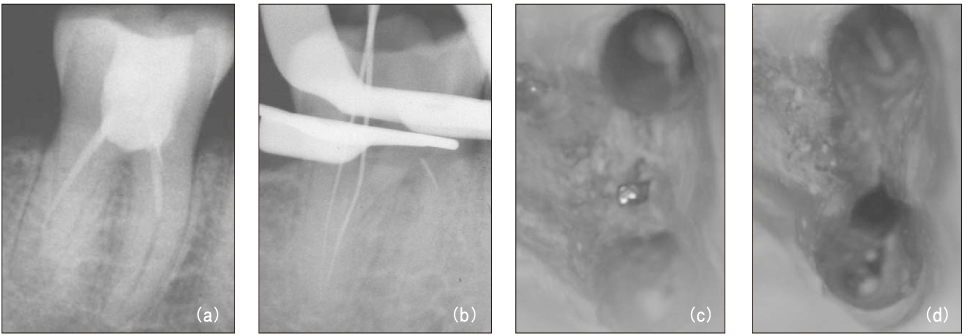

Figure 1

Diagnostic intraoral radiograph (a). Separated file in the mesial root isthmus (b, c) and remove it using ultrasonic device under microscope (d).

Figure 1 Diagnostic intraoral radiograph (a). Separated file in the mesial root isthmus (b, c) and remove it using ultrasonic device under microscope (d).